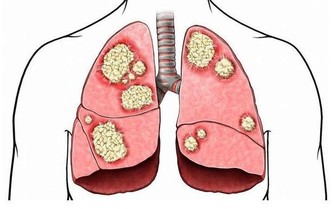

其次是化療和放療。

如果是胃癌早期,治療效果還好,但是,很多胃癌被發現時已是晚期,只能對症處理,盡力延長生命、減輕痛苦,所以早發現很重要。

會的,所以要定期復查,一旦出現復發或轉移,及時治療。